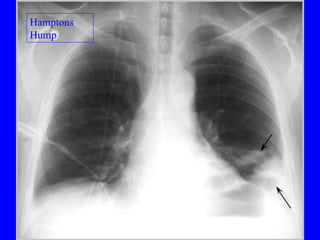

Diagnosis CXR Usually reveals a non specific abnormality.  14% normal Classic abnormalities include: Westermark’s Sign - focal oligemia Hampton’s Hump - wedge shaped density Enlarged Right Descending Pulmonary Artery (Palla’s sign)

PE Hamptons   Hump